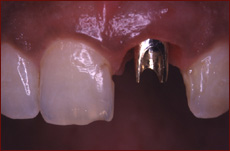

Will my dental implant be esthetic?

Our top priority is to give our patients a beautiful result. This is accomplished in several ways. We assure that the site for the dental implant has adequate hard and soft tissue to support an esthetic implant. When possible, we will place the dental implant at the time of extraction to preserve tissue to support an ideal crown. We also work closely with your dentist to achieve an outstanding result.